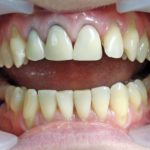

Некачественное протезирование может приносить пациенту множество проблем. Среди них – изменение цвета слизистых оболочек. Если протез установлен неправильно, ухудшается кровоснабжение мягких тканей, они получают меньше кислорода. Появляется образование, похожее на небольшую шишку. Что делать с синей десной, нужно решать незамедлительно, чтобы избежать некроза.

Если после установки протезов десна посинела и болит, попутно появляется чувство легкого онемения, связанного с недостаточным питанием тканей. Человеку становится сложно жевать пищу и даже говорить. Самое печальное, что порой люди считают такие симптомы нормальными, связывая их с привыканием к новым конструкциям. Однако врачи предупреждают: десны фиолетового цвета являются одним из признаков патологии, которую нужно сразу устранять. Поэтому консультация специалиста необходима.